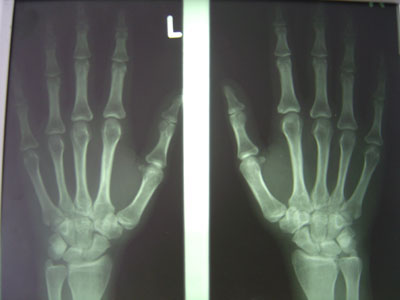

Das Handröntgenbild zeigt folgenden Befund:

Hände dorsopalmar bds.

Wie interpretieren Sie diese Röntgenaufnahme?